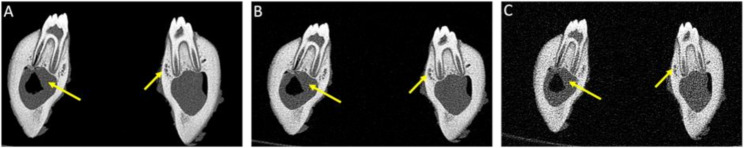

Methods: This ex vivo comparative study of porcine specimens assessed five imaging protocols with both CBCT and PCD-CT at three effective radiation dose levels (high: 360µSv, standard: 145µSv, low: 20µSv) to evaluate image quality, artifact burden, metal artifact susceptibility, and quantitative bone measurements in the mandibular region. Three blinded readers analyzed the data using a 5-point Likert scale (5 = highest to 1 = lowest rating) and performed linear bone measurements at implant planning sites. Statistical analysis included descriptive statistics and inter-reader reliability assessment using intraclass correlation coefficients (ICC).

Results: Each reader evaluated 30 data sets (12 CBCT, 18 PCD-CT), with 24 implant planning sites per imaging protocol. High-dose PCD-CT demonstrated the best image quality and diagnostic interpretability (4.89 ± 0.27), followed by standard-dose PCD-CT and CBCT (4.50 ± 0.73; 4.33 ± 0.61), with low-dose protocols showing intermediate quality with higher artifact burden. In comparison to CBCT, PCD-CT demonstrated superior performance in reducing implant-induced artifacts across all protocols. Quantitative bone measurements showed minimal variability, meeting clinical precision requirements for computer-assisted implant surgery. Both qualitative (ICCs:0.70-0.89; p < 0.001) and quantitative (ICCs:0.79-1; p < 0.001) analyses demonstrated high reliability, regardless of the reader's experience.